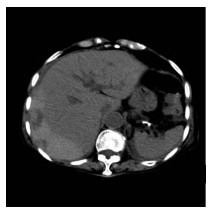

Primary hepatic lymphoma with anemia and hypoproteinemia: A case report

2021, 37(8): 1911-1913. DOI: 10.3969/j.issn.1001-5256.2021.08.034

Abstract(937) HTML (226) PDF (2390KB)(46)

Abstract: